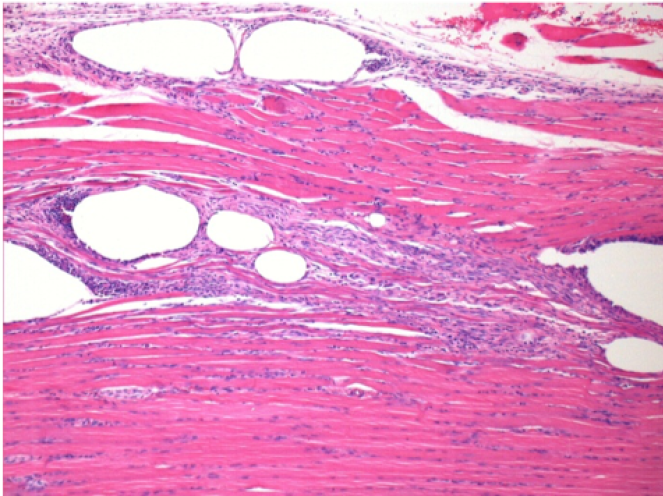

0,5 мл (5x 0,1 мл) підшкірна ін'єкція Ендопіл в праву підшкірну претибіальну ділянку.

Л:200x-Контроль-ПШ

П-10днів-ПШ-200X